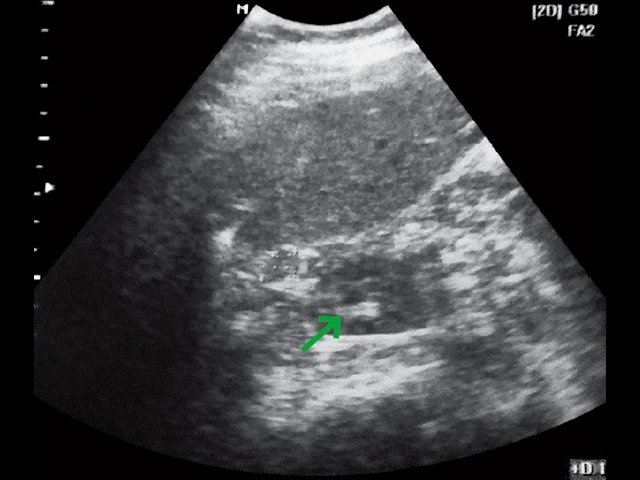

а) В-режим. Забрюшинное образование справа (зеленые стрелки).

б) В-режим. Забрюшинные лимфатические узлы (красные стрелки).